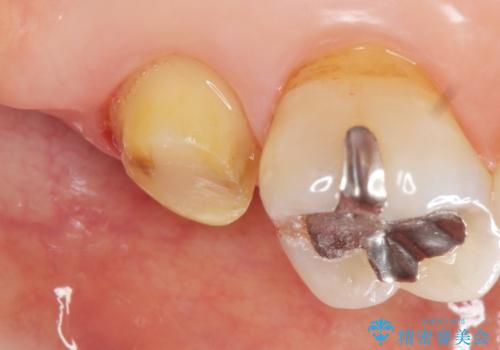

- 根管治療ののち、そのままになっていた歯のクラウン製作を希望され来院されました。

クラウンの将来的な虫歯の再発を防ぐために周囲の歯ぐきを切除することで歯の高さを出し安定した歯周環境にしたのち噛み心地の良いゴールドクラウンを製作します。

クラウンを装着した歯の虫歯の再発を防ぎ長い予後を期待するために削った箇所をしっかりとかぶせる適合の良さが必要はもちろんですが、セメントの漏洩を防ぐためにクラウンの十分な支台高径を歯周外科を行い獲得しました。